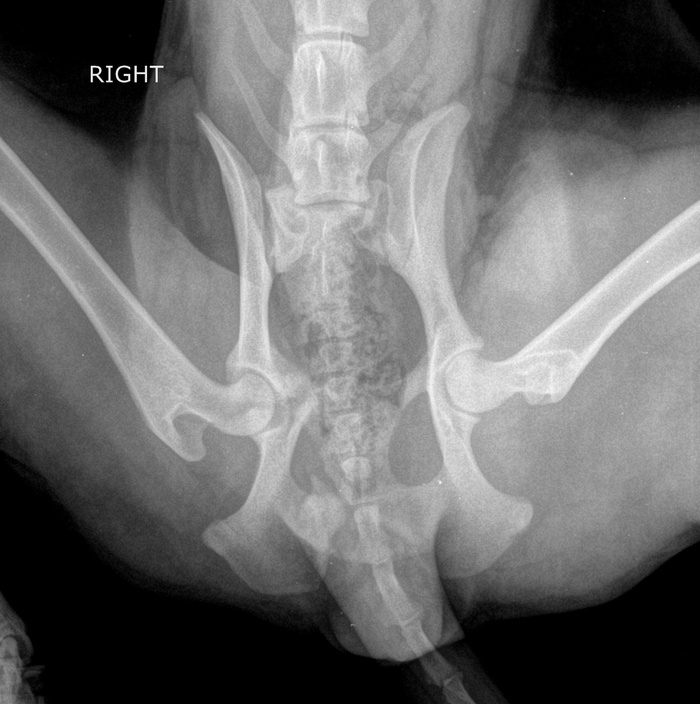

Шейка таза перелом

Шейка таза перелом 111 фото